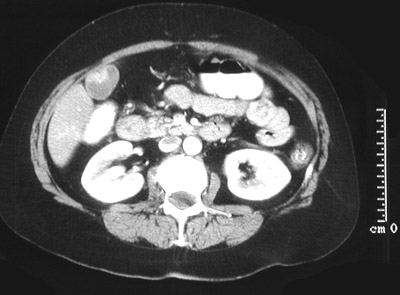

![]() | In the abdominal CT scan view above, there is an irregular mass within the lower portion of the gallbladder, with the inferior tip of the right lobe of liver adjacent to it. This mass proved to be an adenocarcinoma of the gallbladder. In the frame below, the gallbladder can be seen next to the liver. The gallbladder wall is irregular, and there are also scattered densities within the lumen, representing gallstones (up to 90% of gallbladder adenocarcinomas arise in association with gallstones). |